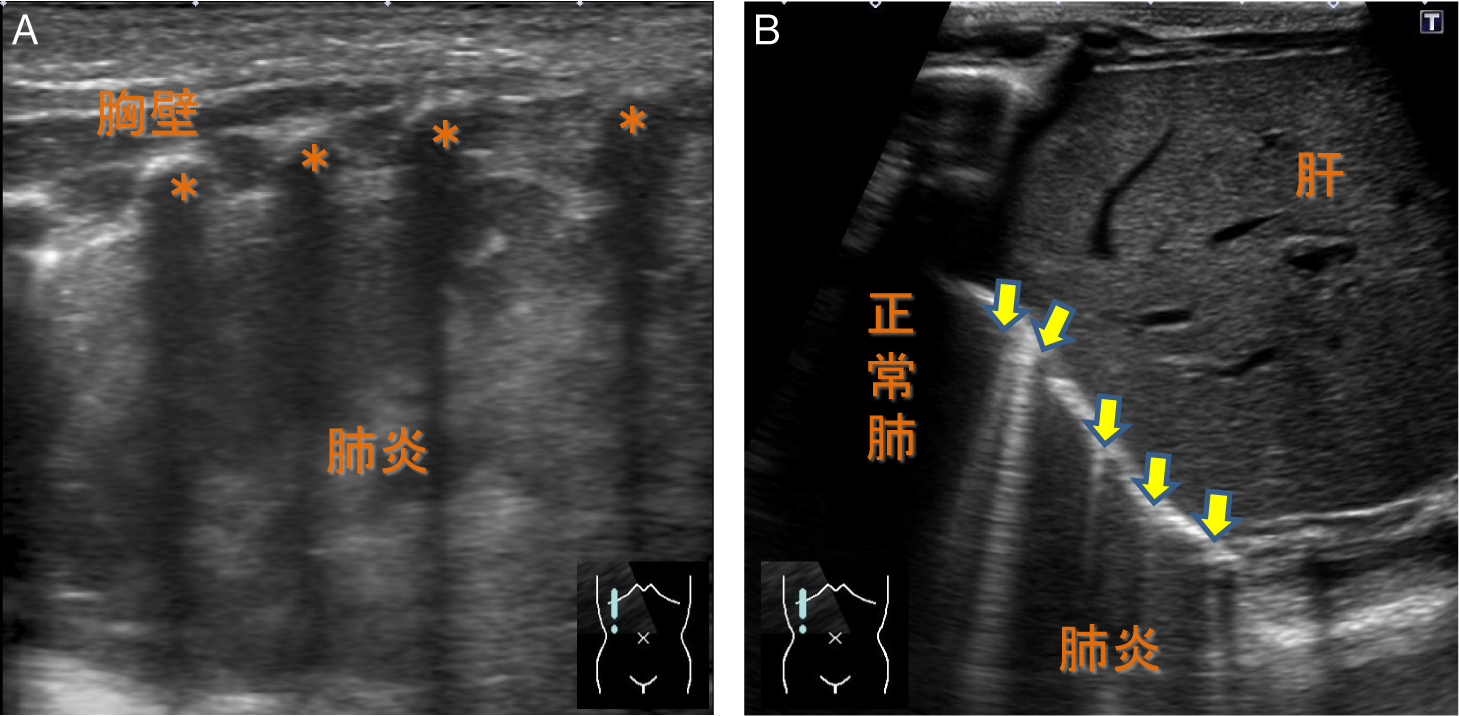

肺炎と無気肺との鑑別は,超音波所見のみからでは困難な場合が多い.無気肺と同様に含気を失った肺が描出される(Fig.14A)と同時に,非区域性分布,浸出物等の貯留による膨隆傾向や胸水など随伴所見の有無などが参考になる場合がある17).また間接所見として,多数のB lineが描出されることがある.1肋間隙に3本以上のB lineが観察される場合にmultiple B linesと呼び,肺内に過剰な水分を含んだ病態とされる(Fig.14B).成人での検討が小児にも応用可能であるのか不明であり,また多重反射(乱反射)に立脚した画像所見は機器の進歩により変容する可能性があり,間接所見を過度に信頼するには慎重であるべきと考える.

A:含気を失った肺が低輝度に描出される.*肋骨

B:別症例.右肺底部に多数のB lineが描出される(→:multiple B lines).肺内の過剰水分を示唆する間接所見とされる.